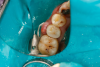

Fig 32. Preparation is completed, caries are removed, sand blasting with potassium carbonate is performed, and matrix band is placed.

Figure 32

Fig 35. Injection filling of cavity preparation with dual-cure bulk-fill flowable composite to a slight overfill.

Figure 35

Fig 36. Injection overfill smoothed with a brush. At this step, it is important not to disturb the margins.

Figure 36